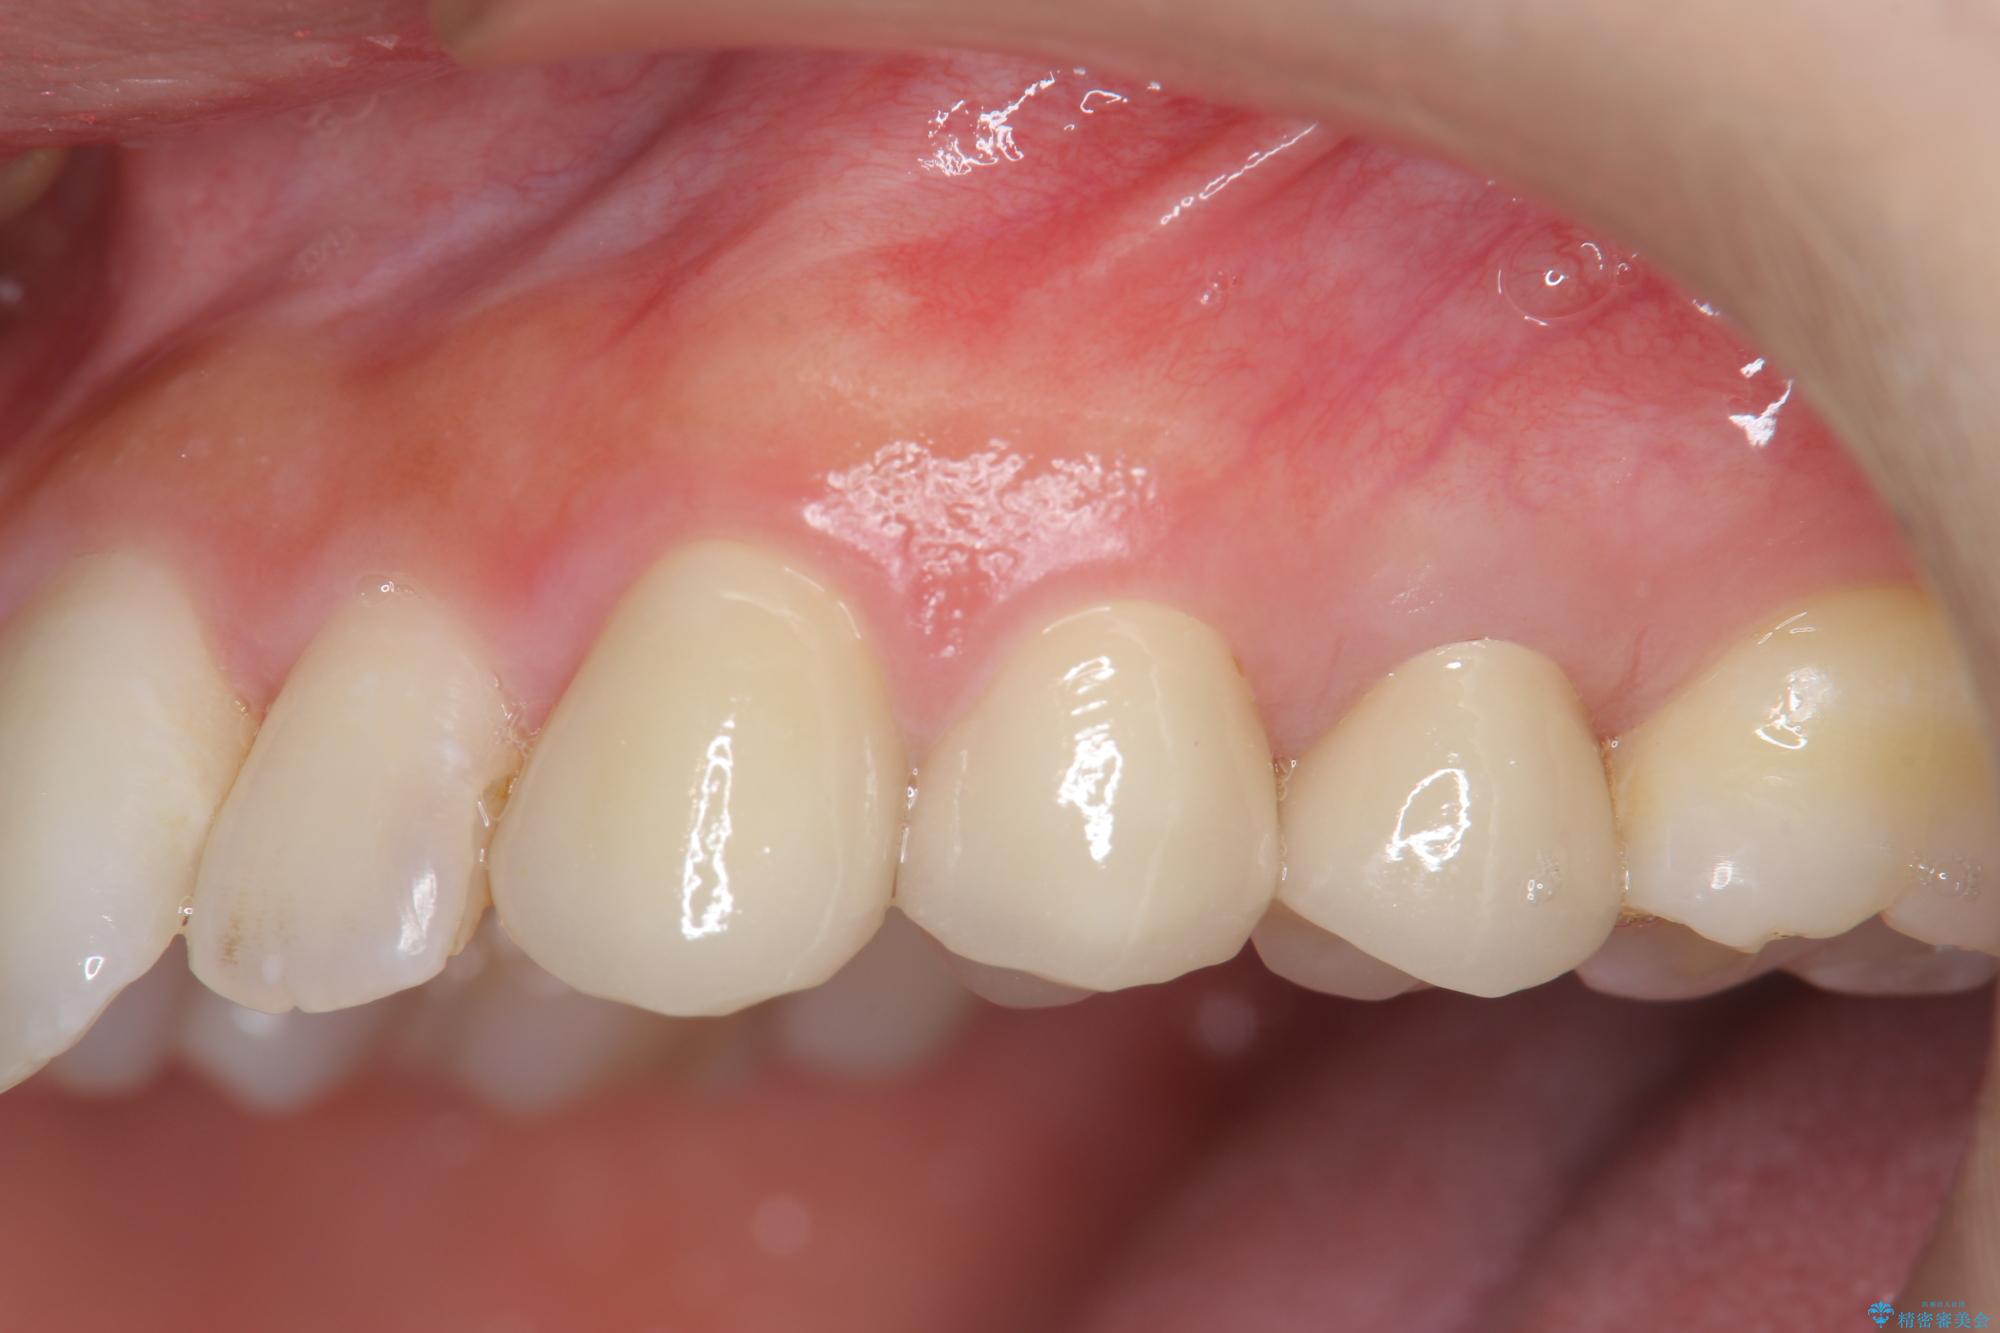

歯の水平・垂直的位置を整備したセラミッククラウン治療

当初、歯ぐきよりも深い虫歯のぞんざいや、歯のポジションに問題がありましたがマルチブラケットを用いた部分矯正を行うことで適切な位置へと歯を移動させ、歯周環境を整えたセラミック治療を行うことができました。